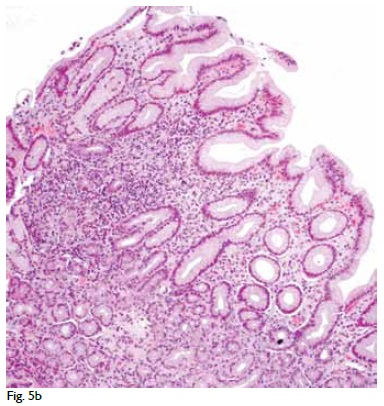

JoL: Nos fragmentos de biopsia obtidos por endoscopia alta não se observaram alterações relevantes. Nos fragmentos obtidos por endoscopia baixa salientava-se a existência de ulceração no cego (Fig. 5A) e alterações inflamatórias com actividade, sem distorção arquitectural, no ascendente, transverso e descendente, com metaplasia de células de Paneth, tal como acontece na doença de Crohn (Fig. 5B).

JoL: Nos fragmentos de biopsia obtidos por endoscopia alta não se observaram alterações relevantes. Nos fragmentos obtidos por endoscopia baixa salientava-se a existência de ulceração no cego (Fig. 5A) e alterações inflamatórias com actividade, sem distorção arquitectural, no ascendente, transverso e descendente, com metaplasia de células de Paneth, tal como acontece na doença de Crohn (Fig. 5B).